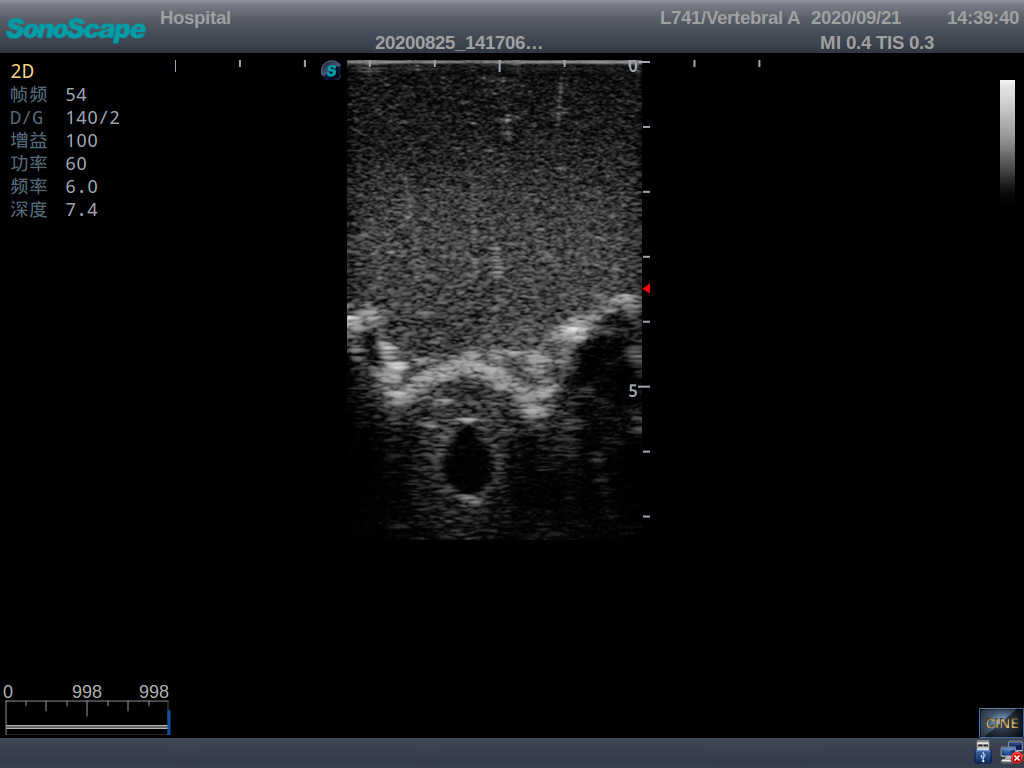

Adult Lumbar Puncture Ultrasound Training Model

Model TYE1549.2

This model is an ideal choice for ultrasound-guided adult lumbar puncture training with true-to-life skin feel and touch, accurate anatomical structures as well as real clinical ultrasound images. Realistic resistance to needle tips and correct landmarks provide excellent hands-on experience.

2)  Real clinical ultrasound images

3)  Compatible with various real ultrasound machines